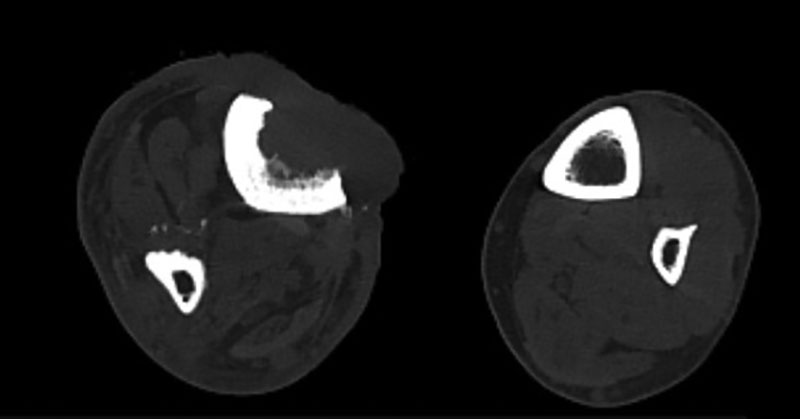

Данные компьютерной томографии (КТ) от 31 августа 2021 г.: КТ-картина в большей степени соответствует опухоли кожи правой голени с врастанием в большеберцовую кость (рис. 3 и 4). Деформация и изменение структуры костей правой голени не противоречат последствиям остеомиелита. По итогам проведения врачебной комиссии было принято решение о назначении иммунотерапии анти-PD-1-моноклональным антителом ниволумабом 480 мг внутривенно капельно один раз в 28 дней. После двух введений ниволумаба проведен контроль в динамике.

КТ правой нижней конечности от 8 декабря 2020 г.: визуализируется грубый эксцентрический дефект большеберцовой кости справа 40 × 20 × 28 мм, в образованный дефект костной ткани пролабируют мягкие ткани голени.